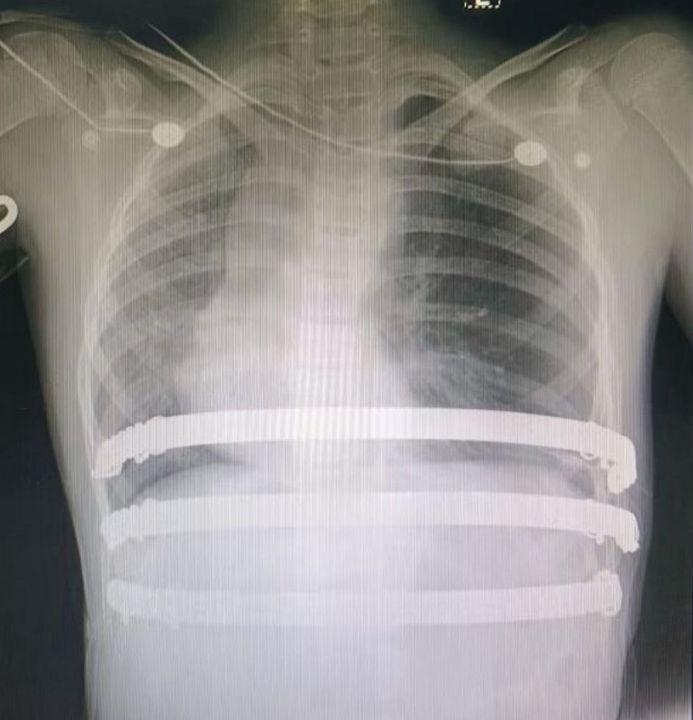

Three incisions, each approximately 3 cm in length, were made at the midline and on both sides of the chest wall. The chest wall first underwent pre-shaping, followed by placement of two bars to perform the Wung procedure, correcting the depression deformity. Subsequently, the Wenlin procedure was performed to further optimize the chest wall contour and achieve a more ideal appearance (a minor localized protrusion occurred during correction due to the overall rigidity and stability of the thoracic structure). The surgery proceeded smoothly and was completed within one hour. Postoperatively, the patient’s chest wall deformity was fully corrected, and normal appearance was restored.